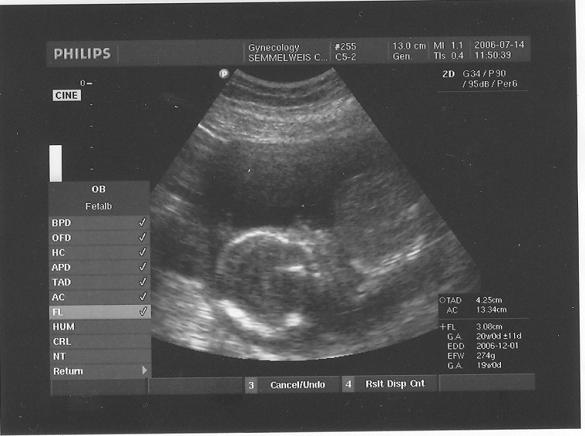

A 10. heti ijedség után szerencsére semmi komoly nem történt

, nagyon jól vagyunk. 20. heti UH-n minden rendben talált a doki, a hematóma eltűnt, a baba a korának teljesen megfelelő méretekkel rendelkezik (20+1-en voltunk, a gép a méretekre 20+2-öt írt). Viszont én nagyon renitens voltam, az APF-t nem csináltattam meg. Ennek több oka is van: 1. nagyon megbízhatatlannak tartom, 2. nekem Nátánnál és Hannánál is elkeveredett (más védőnői körzetbe ment, csak több hét után kaptam meg